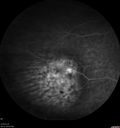

88 year old female with melanosis oculi and 2.5 mm elevated choroidal melanoma. She also has AMD with geographic atrophy. The right eye is the better eye. The left eye had a macular hemorrhage from wet AMD and breakthrough vitreous hemorrhage.